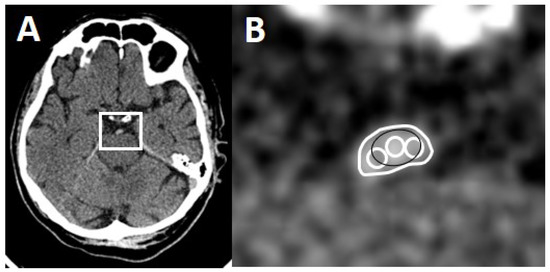

One rater (board-certified stroke neurologist) blinded to clinical and imaging results measured absolute thrombus density in all 56 patients on all NECCTs with all three available slice thicknesses (0.625, 2.5 and 5 mm). Three different methods were used. Method 1: one round or oval region of interest (RoI) was drawn onto the most hyperdense part of the thrombus [10]. Method 2: three small (or two if too small) oval or circular RoIs were drawn onto the thrombus [7]. Method 3: the outline of the whole thrombus was delineated by carefully excluding pixels outside the thrombus as a RoI on each slice of the NECCT [11]. For Method 2 and 3, the sum of the obtained density values was then divided by the number of drawn RoIs. Densities > 100 HU were considered calcifications and were excluded (Figure 1).

Figure 1.

Methods of thrombus delineation. (A) Axial CT section with a hyperdense basilar artery. (B) Magnified region of interest (white box) with the three methods of thrombus delineation. Method 1: black RoI, Method 2: three white circles, Method 3: large white RoI.